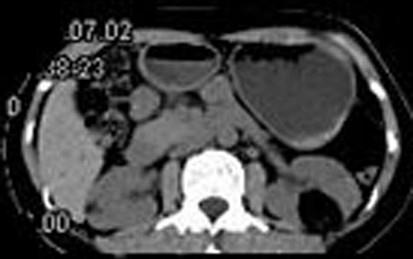

问题 女,38岁,体检时B超在左肾探及一中强回声光团,边界清,内部回声均匀,CT检查如图所示,下列说法正确的是 ( )

选项 A、考虑为左肾血管平滑肌脂肪瘤 B、考虑为左肾脂肪瘤 C、病灶与周围肾组织界限清楚 D、病灶密度为脂肪密度 E、左肾中部靠后方可见一类圆形低密度病灶

答案 BCDE